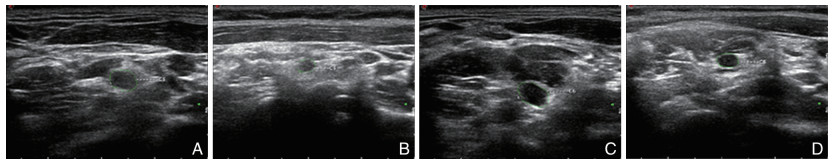

Significance and mechanism of neuroultrasound combined with neuromagnetic resonance imaging in the diagnosis and treatment of Guillain-Barré syndrome

SHI Peng, WU Xinyu, HUAI Yushui, SONG Hongwei, NIAN Di

2025, 23(8): 1292-1297. doi: 10.16766/j.cnki.issn.1674-4152.004118

Abstract:

Objective  To explore the significance and mechanism of neuroultrasound and neuromagnetic resonance imaging in the diagnosis of Guillain-Barré syndrome (GBS).  Methods  A total of 43 GBS patients who were first diagnosed at the First Affiliated Hospital of Bengbu Medical University from October 2021 to February 2025 were enrolled, and 24 patients with normal physical examination were enrolled as control group. Based on neurophysiological examinations, the GBS were classified into two subtypes: acute inflammatory demyelinating polyneuropathy (AIDP) and acute motor axonal neuropathy (AMAN). Neuroultrasound and neuromagnetic resonance imaging were performed on all subjects. The cross-sectional area of the cervical nerve roots and peripheral nerves (CSA) was measured by neuroultrasound, and the CSA of the cervical nerve root and lumbar sacral nerve root was measured by neuromagnetic resonance imaging. The degree of neurological impairment in GBS was assessed using the GBS disability scale scores (GDSS), and the correlation between CSA values and the degree of neurological deficit was evaluated. Peripheral venous blood was collected, and the levels of pyroptosis-related inflammatory factors in peripheral blood were measured using ELISA.  Results  Compared with the control group, the nerve roots and peripheral nerves of the limbs in the AIDP group and the AMAN group were thickened, and the CSA value was increased. Among them, nerve ultrasound showed that there were statistically significant differences in C5 and C6 among the three groups (H=20.216, P < 0.001; H=12.452, P=0.002), and the magnetic resonance imaging results showed that compared with the AMAN group and the healthy control group, the CSA values of C4-C8 and L3-S1 in the AIDP group were significantly increased, and the differences were statistically significant (P < 0.01). The CSA value of peripheral nerves was positively correlated with the degree of neurological deficit (P < 0.05). Pyroptotic inflammatory factors were higher than those in the control group, and the difference was statistically significant (P < 0.05).  Conclusion  The elevated CSA values of nerve roots and peripheral nerves, as well as neurological deficits in GBS, may be associated with the inflammatory cascade triggered by pyroptosis pathway activation. The detection of peripheral blood inflammatory cytokines combined with neuroimaging may facilitate early diagnosis of GBS and provide novel insights for its clinical management.